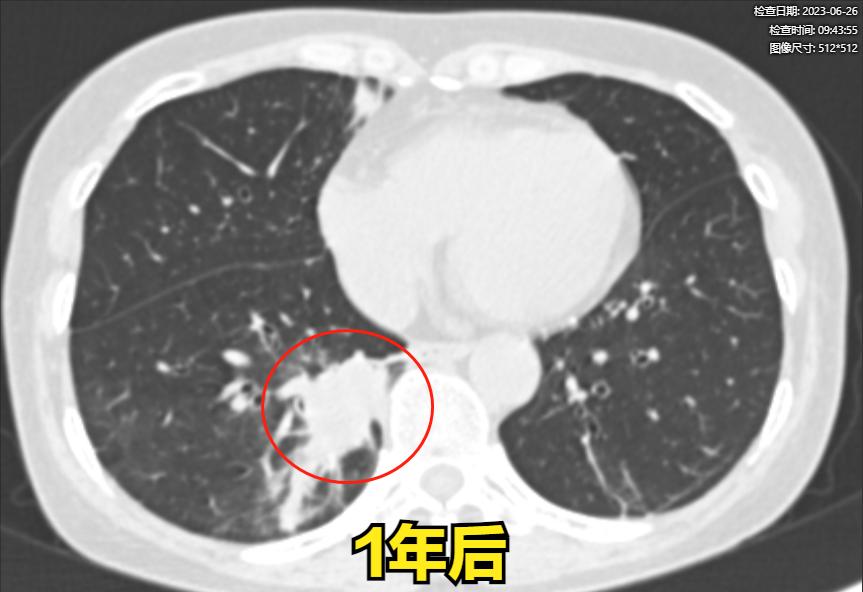

男性,59岁,于1年前(2021年5月29日)出现咳嗽症状,发现右下肺有占位病变。当时检查发现有少量胸水,病灶边界模糊。经抗感染治疗后进行复查,发现病灶明显增大,不能排除恶性病变的可能性。我建议进行穿刺活检以进一步明确诊断。虽然我们与家属进行了多次交流并建议活检,但家属担心活检后可能引起病变扩散。

73岁 男性 患者于4个月前发现右肺出现占位性病变。当时他住院在一家顶级医院接受治疗,但病灶的大小并不小。之前我也阅片提示恶性的,尽管都住院期治疗了,医生也建议进行活检以明确诊断,但患者拒绝了。因此,他的病情没有得到明确的解决,最后他选择回家观察。4个月后,他再次找到我进行检查,发现病灶比之前明显增大,同时出现了恶性征象,我们开始考虑是否为肺癌。最终,病理检查结果也证实了肺癌

这位朋友特别遗憾,和家属之前进行了长时间的沟通,但在4个月前他们不愿意进行进一步的检查。由于病灶的恶性程度较高,4个月后病情明显恶化,胸膜也受到了累及,这可能导致失去直接手术的机会。如果在4个月前进行了肺叶切除手术,康复的可能性会更高。